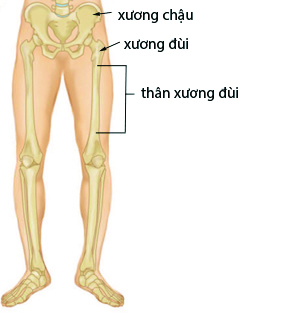

Gãy thân xương đùi được giới hạn từ bờ dưới mấu chuyển lớn đến bờ trên lồi cầu ngoài 5cm. Xương đùi là một xương có sự chống đỡ đặc thù đối với mọi chấn thương do cấu trúc giải phẫu của nó. Đó là do 3 độ cong sinh lý và sự bố trí vùng chịu lực.